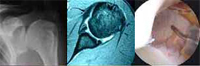

The shoulder joint is formed by the proximal humerus, scapula and clavicle. It is divided into two articular spaces, the subacromial space and the glenohumeral joint. These two spaces are separated by the rotator cuff tendons.

El tratamiento inicial es conservador: rehabilitación y medicación, siendo necesario en ocasiones realizar infiltraciones. Si no existe mejoría el tratamiento es quirúrgico. Se realiza una artroscopia del hombro, se elimina el engrosamiento del acromion y se realiza la reparación de los tendones.

El tratamiento inicial es conservador: rehabilitación y medicación. En ocasiones puede ser necesario realizar infiltraciones. Si no existe mejoría el tratamiento es quirúrgico. Se realiza una artroscopia del hombro y se elimina el engrosamiento del acromion con fresas motorizadas. La recuperación será completa al cabo de unos meses.

El tratamiento inicial es conservador, pero si este fracasa se produce una luxación recidivante yse tendrá que recurrir a la cirugía. En deportistas jóvenes se puede realizar la reparación quirúrgica tras la primera luxación. Se reparan las lesiones de los ligamentos dañados con tornillos y suturas que se implantan por vía artroscópica. Posteriormente se realiza rehabilitación.